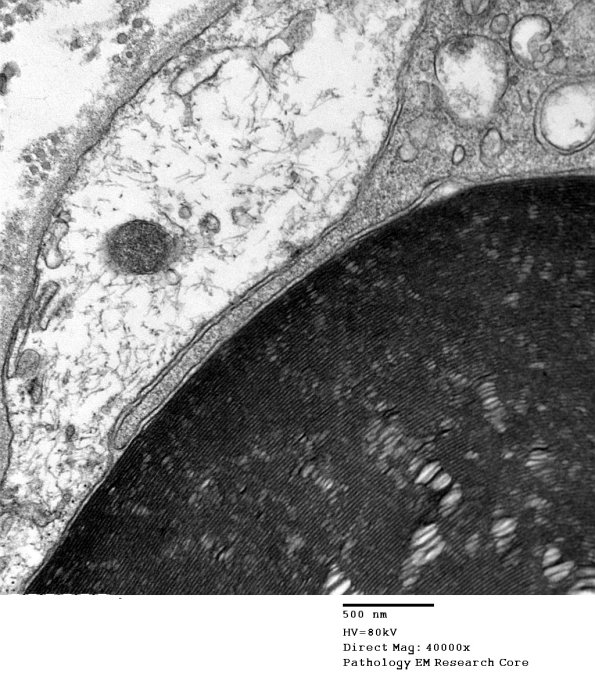

Notice a finger of the macrophage pushing the Schwann cell pale process away from the underlying myelin. (electron micrograph)